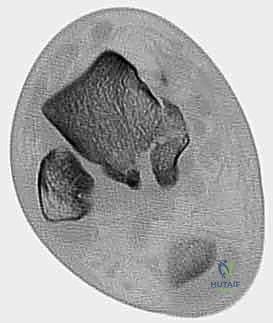

3. التصوير المقطعي المحوسب (CT Scan) - المعيار الذهبي

في عيادة الأستاذ الدكتور محمد هطيف، يُعتبر التصوير المقطعي المحوسب ثلاثي الأبعاد (3D CT Scan) إجراءً روتينياً وحتمياً لأي كسر في عظم الكاحل. توفر الأشعة المقطعية تفاصيل دقيقة للغاية عن خطوط الكسر، مدى التفتت (Comminution)، وحجم الإزاحة المفصلية التي لا يمكن رؤيتها بالأشعة السينية العادية. بناءً على هذه الصور، يقوم الدكتور هطيف ببناء استراتيجية الجراحة (أين سيفتح، ما نوع الشرائح والمسامير التي سيستخدمها، وكيف سيعيد بناء العظم).